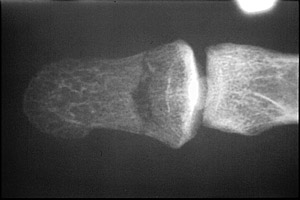

- Click on the image for a larger versionAAP radiograph of the first digit. This reveals a transverse fracture through the distal phalanx of digit one.

- Click on the image for a larger versionBLateral radiograph of the first digit. There is a depressed fracture of the distal phalanx.